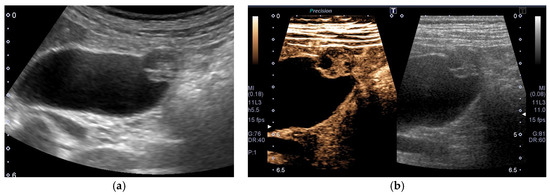

Figure 1. Alteration of US images with postural changes. In the supine position, GBC in the fundus was obscured by reverberation artifacts (a), but a high-frequency probe can delineate the GBC in the left lateral decubitus position (b).